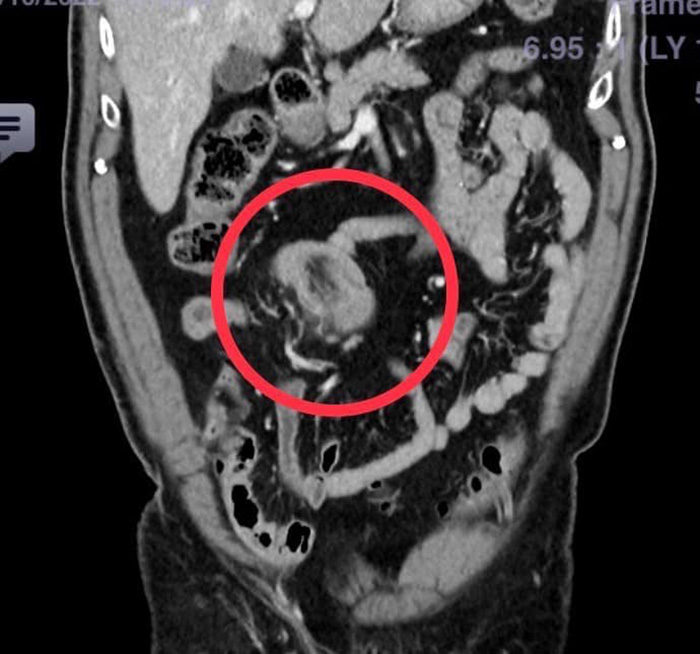

แพทย์ห้องฉุกเฉิน เห็นว่าผู้ป่วยเป็นผู้สูงอายุและเป็นมานาน ควรจะได้รับการตรวจวินิจฉัยโดยละเอียด จึงปรึกษาอายุรแพทย์ ศัลยแพทย์ และรังสีแพทย์ ไปพร้อม ๆ กัน จนได้ภาพรังสีจากเอกซเรย์คอมพิวเตอร์ออกมา พบว่ามีส่วนของลำไส้เล็กส่วนปลายกลืนกัน จึงวางแผนรักษาโดยการผ่าตัดทันที